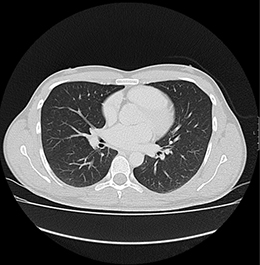

Bei der CT handelt es sich um ein röntgendiagnostisches computergesteuertes Verfahren. Bei der Untersuchung liegt der Patient auf einer beweglichen Liege, die innerhalb weniger Sekunden durch eine kurze Röhre fährt. In dieser wird er von einem Röntgenstrahler umkreist, wobei schichtweise Aufnahmen aus vielen Richtungen entstehen. Aus diesen ergibt sich bei modernen Multislice-Scannern ein dreidimensionaler Datensatz, der anschließend an einem Hochleistungscomputer durch den Radiologen ausgewertet wird.

Die CT wird bei diversen Erkrankungen zur Klärung von Organveränderungen, Blutungen und Flüssigkeitsansammlungen sowie auch bei Tumorverdacht durchgeführt. Auch Verengungen und Verkalkungen in den hirnversorgenden Gefässen, der Körperschlagader, den Herzkranzgefäßen oder Tumoren im Darm können heute mittels CT nachgewiesen werden. Hinsichtlich bestimmter Erkrankungen der Lunge und des Bauchraumes und hinsichtlich der Untersuchung von schwerkranken oder beatmeten Patienten gibt es derzeit häufig keine strahlungsfreien Alternativen. Die CT ist daher in vielen Fällen eine unverzichtbare radiologische Methode zur Erfassung krankhafter Veränderungen im menschlichen Körper, deren Nutzen das Strahlenrisiko bei weitem übertrifft.